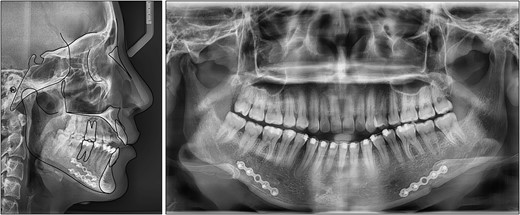

On a lateral cephalometric evaluation, the patient had a skeletal class I relationship (point A-nasion-point B angle, 4.0°) with a hyperdivergent facial pattern (Frankfort mandibular angle, 32.5°) (Table 1). The panoramic radiograph showed the presence of all teeth including the third molars (Fig. 2). The patient was diagnosed with an iatrogenic open bite and class II malocclusion on a skeletal class I relationship.